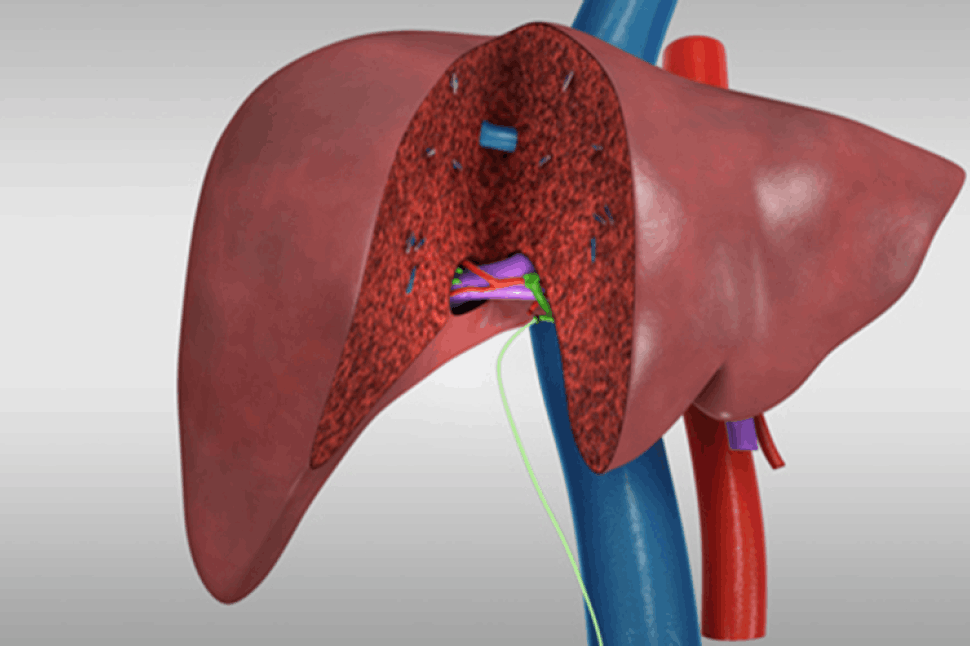

Что такое Хирургическая трансплантация печени?Трансплантация печени - это замена больной печени пациента на здоровую печень донора. Это жизненно важная процедура для пациентов с конечной стадией заболевания печени или острой печеночной недостаточностью, обеспечивающая им комплексное до- и послеоперационное лечение.